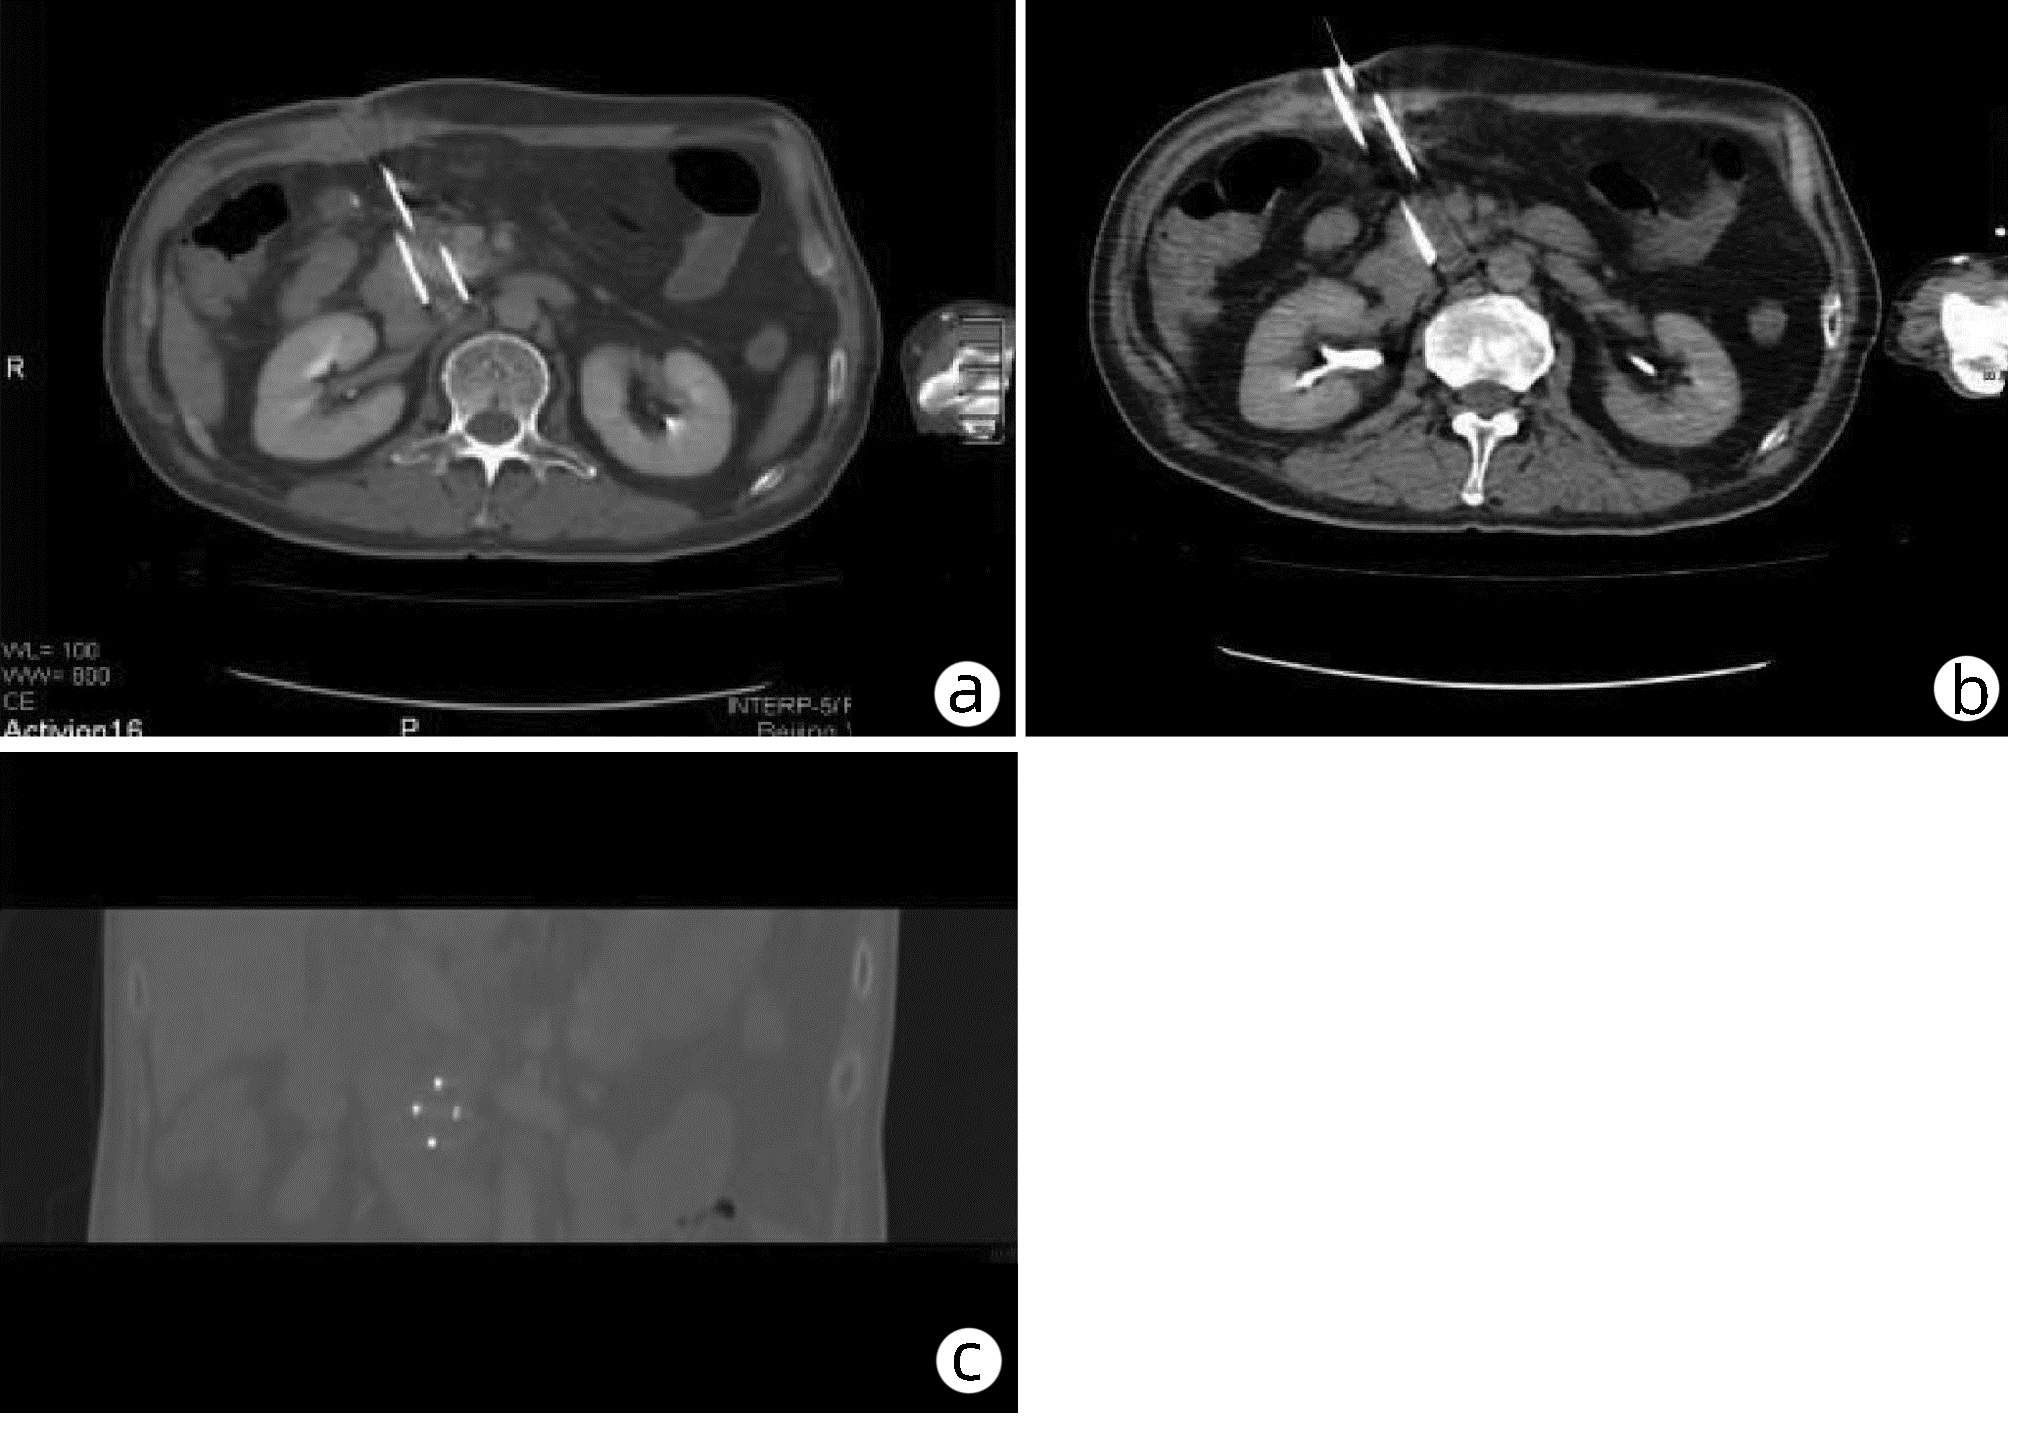

Establishment and application of a preoperative grading system for resectable pancreatic cancer

Chengfang WANG, Zhijiang WANG, Weilin WANG

2022, 38(10): 2325-2333. DOI: 10.3969/j.issn.1001-5256.2022.10.023

Abstract(945) HTML (545) PDF (2058KB)(65)

Abstract:

Objective  To investigate the risk factors for early recurrence of resectable pancreatic cancer and the establishment and application of a grading system.  Methods  A retrospective case-control study was conducted among 303 patients with resectable pancreatic cancer who underwent radical resection in Department of Hepatobiliary and Pancreatic Surgery, The Second Affiliated Hospital of Zhejiang University School of Medicine, from March 2015 to June 2021, and according to the presence or absence of early recurrence (within 6 months after surgery), the 283 patients directly operated on were divided into early recurrence group with 95 patients and non-early recurrence group with 188 patients; 20 patients who received neoadjuvant therapy before surgery were enrolled as neoadjuvant therapy group. Observation indicators included general information, preoperative imaging data, preoperative laboratory data, routine blood test/blood biochemistry and derived indicators, tumor markers, and coagulation markers, and follow-up was conducted to observe recurrence-free survival. The t-test was used for comparison of normally distributed continuous data between two groups, and the Mann-Whitney U test was used for comparison of non-normally distributed continuous data between two groups; the chi-square test was used for comparison of categorical data between two groups. A multivariate Logistic regression analysis was used to investigate the risk factors for early recurrence in patients with pancreatic cancer, and the receiver operating characteristic (ROC) curve was used to determine the optimal cut-off value of each indicator. The Kaplan-Meier curve was plotted, and the Log-rank test was used for comparison of recurrence-free survival time between groups.  Results  The univariate analysis showed that compared with the non-early recurrence group, the early recurrence group had significantly lower body mass index (BMI) and triglyceride and significantly higher CA19-9, CA242, CA125, and plasma fibrinogen (all P < 0.05). The multivariate logistic regression analysis showed that BMI (odds ratio [OR]=1.150, 95% confidence interval [CI]: 1.038-1.273, P=0.007), plasma fibrinogen (OR=2.513, 95%CI: 1.355-4.663, P=0.003), and CA242 (OR=2.482, 95%CI: 1.067-5.774, P=0.035) were independent risk factors for early recurrence in patients with resectable pancreatic cancer. BMI, CA242, and plasma fibrinogen were included in the grading system, with a cut-off value of 23.00 kg/m2, 30.0 U/mL, and 4.00 g/L, respectively. BMI < 23.00 kg/m2 was counted as 1 point, otherwise it was counted as 0 point; CA242≥30.00 U/mL was counted as 1 point, otherwise it was counted as 0 point; plasma fibrinogen ≥4.00 g/L was counted as 1 point, otherwise it was counted as 0 point; the total score was 0-3 points. The patients in both the early recurrence group and the non-early recurrence group were scored, and the results showed that the early recurrence group had a significantly higher score than the non-early recurrence group [2(0-3) points vs 1(0-3) point, Z=-5.339, P < 0.001]. The Kaplan-Meier curve analysis showed that there was a significant difference in time to recurrence between groups (χ2=28.116, P < 0.001), and the higher the score, the shorter the expected time to recurrence. The patients with 3 points were defined as high-risk group and those with 0-2 points were defined as low-risk group, and the early recurrence rate was 84.6% in the high-risk group and 31.2% in the low-risk group.  Conclusion  The grading system based on BMI, plasma fibrinogen, and CA242 can reliably predict postoperative recurrence.